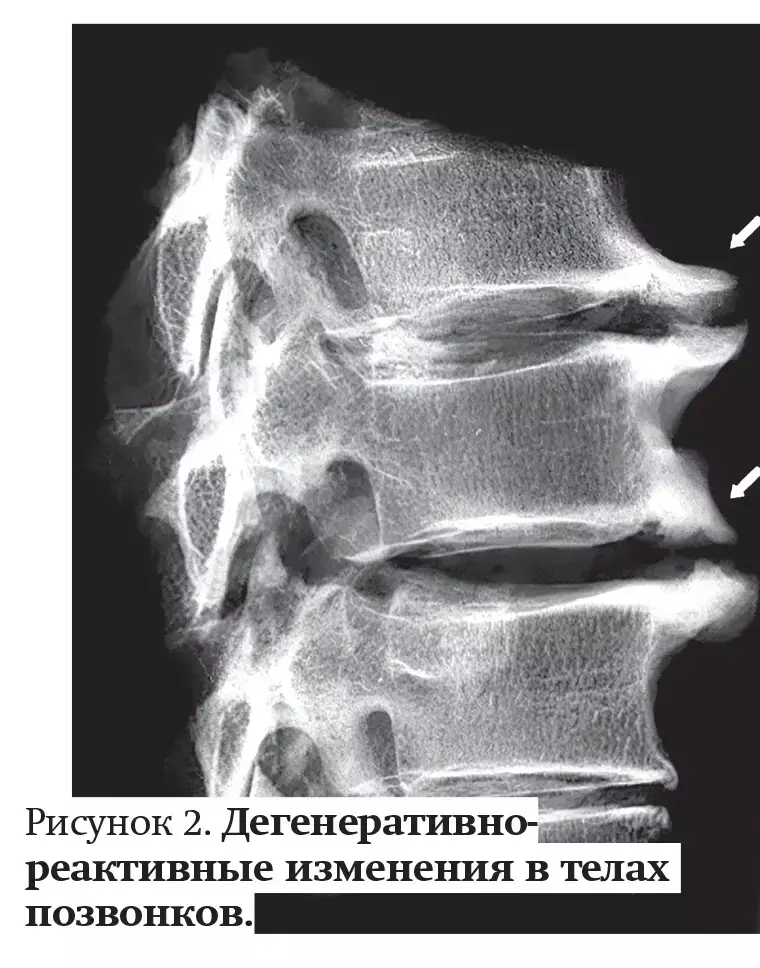

Дегенеративно-реактивные изменения в телах позвонков проявляются в виде краевых костных разрастаний (остеофитов) и субхондрального склероза (см. рис. 2). Краевые костные разрастания являются проявлением компенсаторной приспособительной реакции в позвонках на нагрузку, которая приходится на измененный диск.